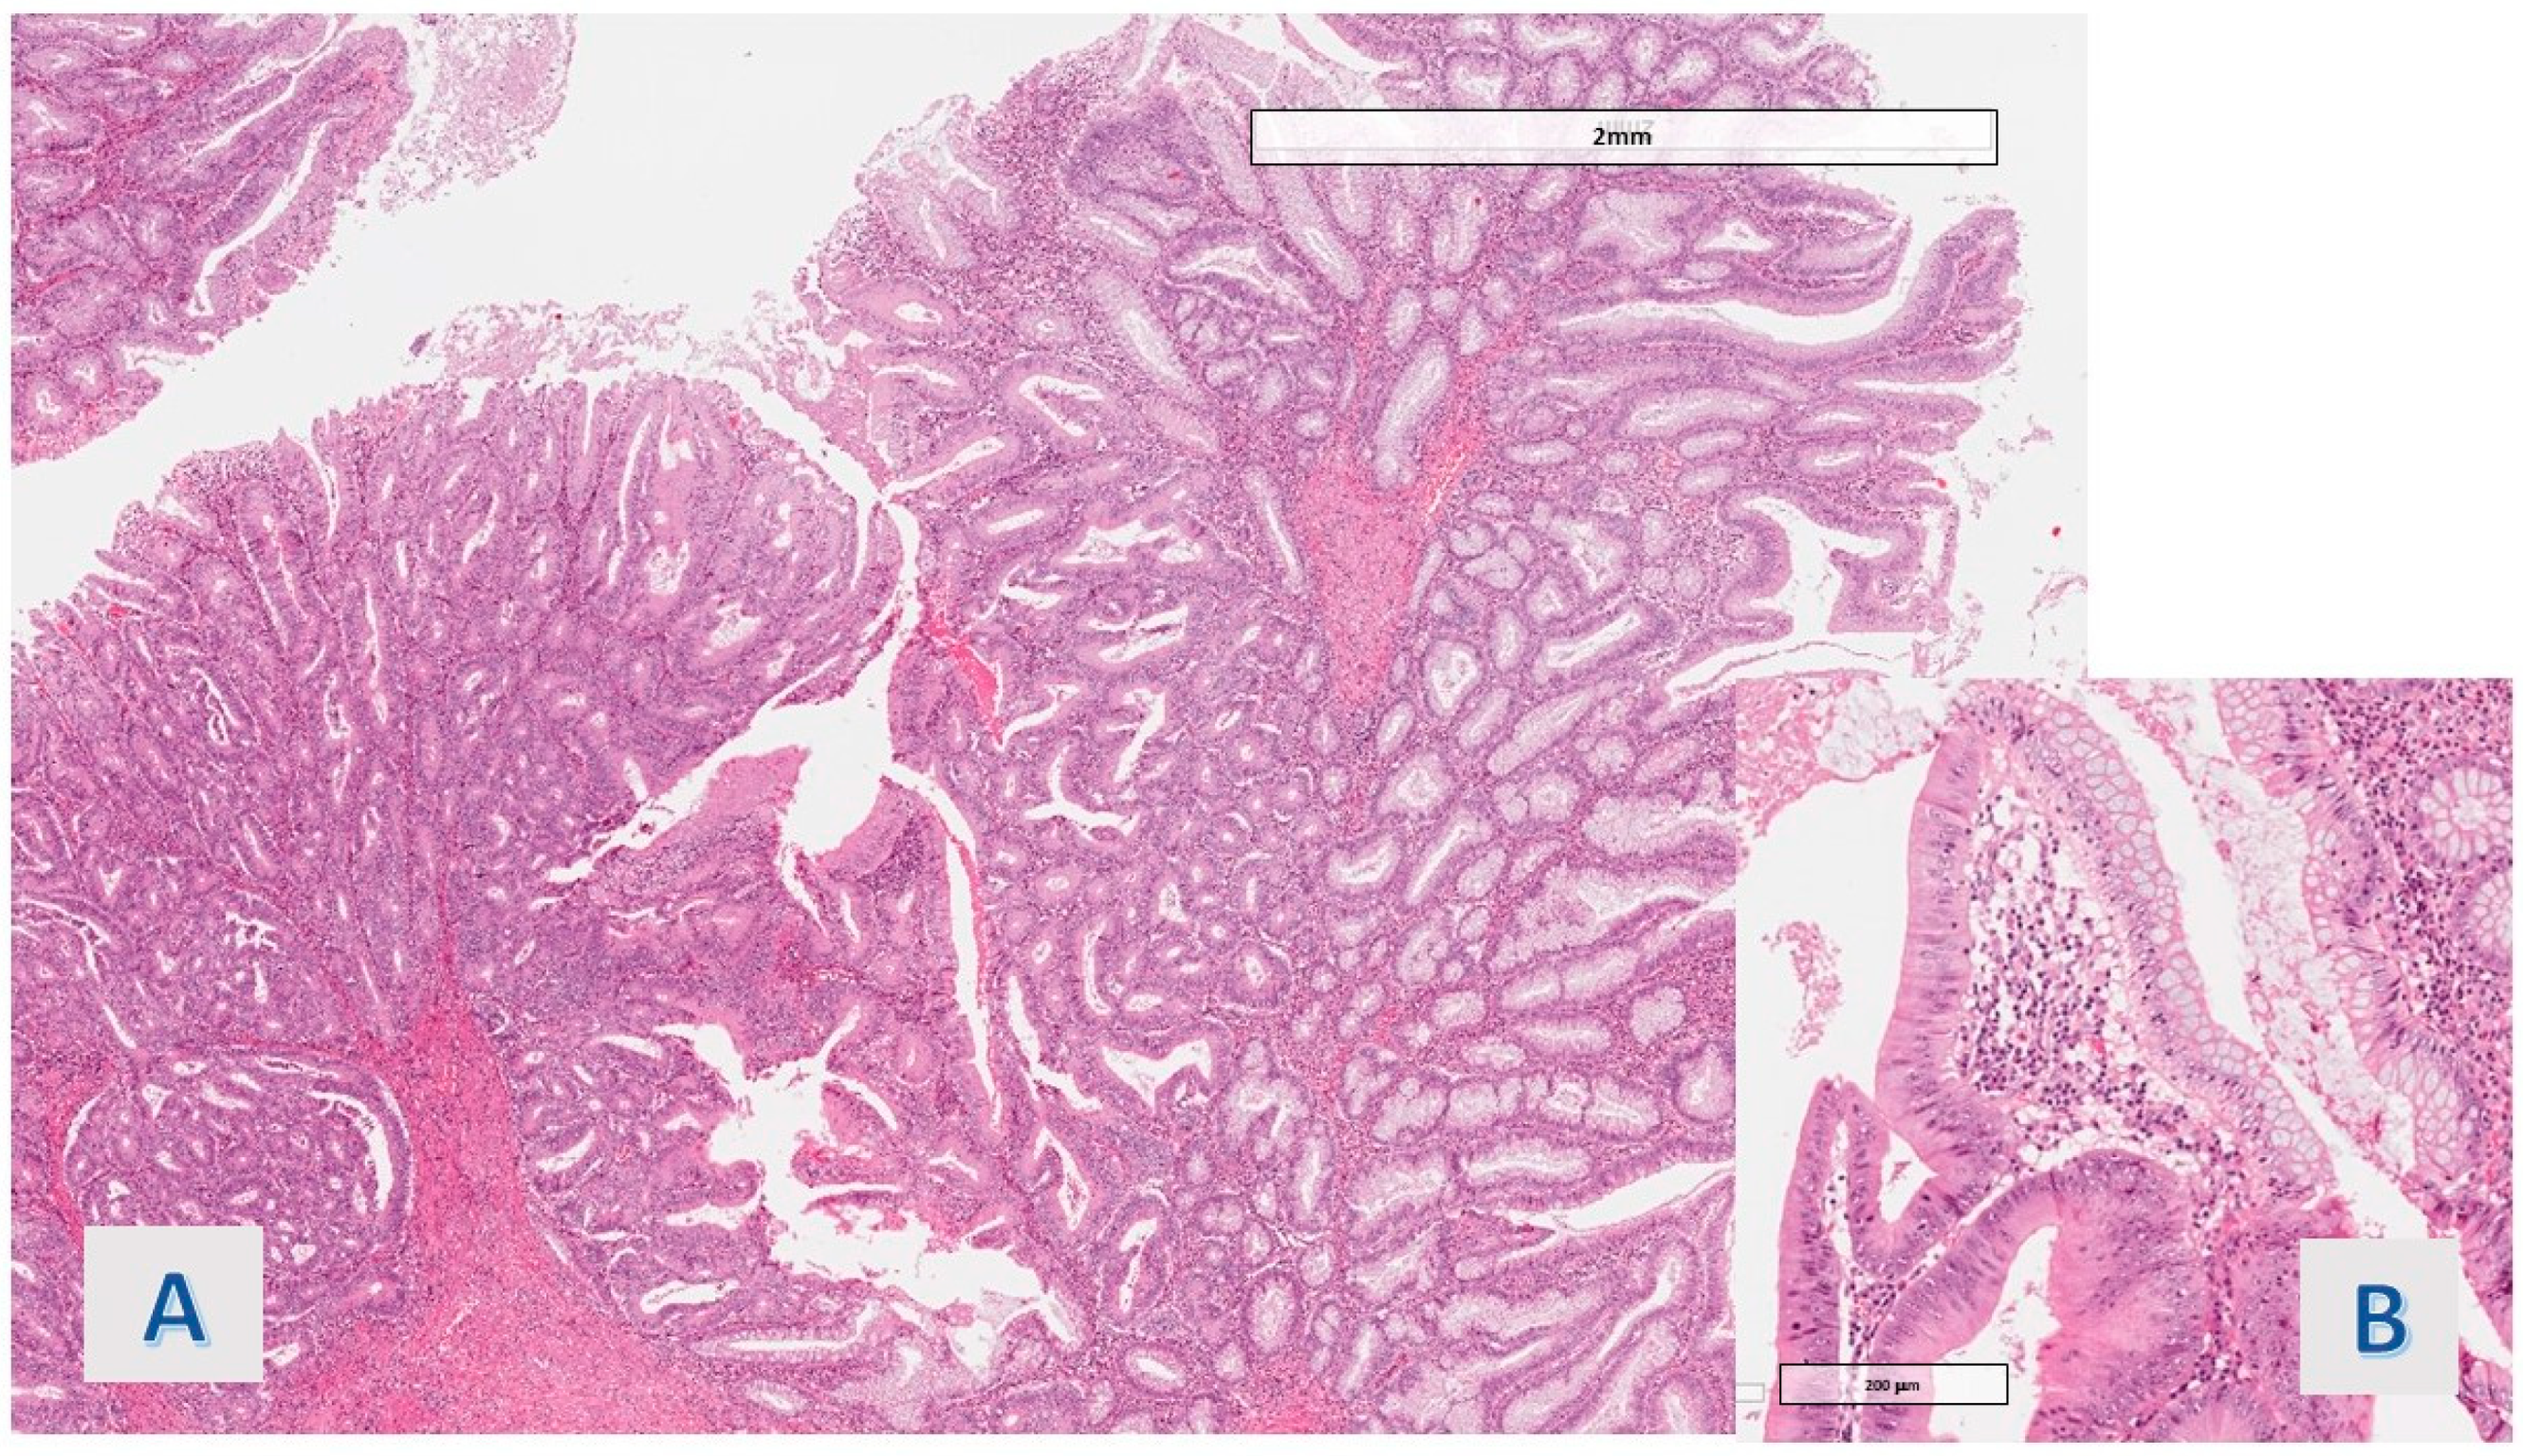

The protruding lesions were coated by an epithelium with hyper mucinous changes (adopting the criteria defined in Section 2) in 11 of the 20 cases (55%) (Figure 1), while the mean rate of the involved samples for a single case was 36.5%. In 9 cases (45%), the hyper mucinous proliferations were associated with hyperplastic/regenerative changes with mild nuclear atypia and mucin depletion. Data about the distribution of IBD subtypes, occurrence of associated conventional (adenomatous) dysplasia, existence of gastric metaplasia (a benign reactive change associated with chronic disease), and grade of activity (in all cases, active disease was detected, except for 1 case in the hyper mucinous group) were matched in the two groups (see Table 2). Associated dysplasia had high-grade features in the case of the group with hyper mucinous changes (Figure 2) and low-grade in the case of the other group (residual low-grade dysplasia after a previous resection for cancerous polyp—pT1 adenocarcinoma).

Figure 2. Case 1: Transition area between dysplastic adenomatous villous structures and hyper mucinous villous structures. (A) hem eos (O.M. 40×), (B) hem eos (O.M. 200×).